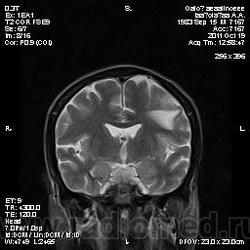

Молодой человек, жалуется только на головные боли и слабость в правой руке и ноге (около месяца).

Пациент полуасоциальный, нельзя исключить анамнез наркоманский....

ППН (включая ячейки пирамидок и сосцевидные отростки) тотально заполнены жидкостным компонентом...

Колеги, спасибо за высказывания. В данном случае про наркоманский анамнез указано не спроста... Есть мнение, что в этом лежит точка отсчета.... По поводу абсцесса и гематомы - не согласен; по поводу первого - нет соответствющей клиники, по поводу второго - не характерна локализация и сигнальные характеристики. Не буду томить общественность касательно собственного мнения. Есть две гипотезы, о которых думается в данном случае: прогрессирующая лейкоэнцефалопатия и новообразование... Но без контраста их не разрешить...